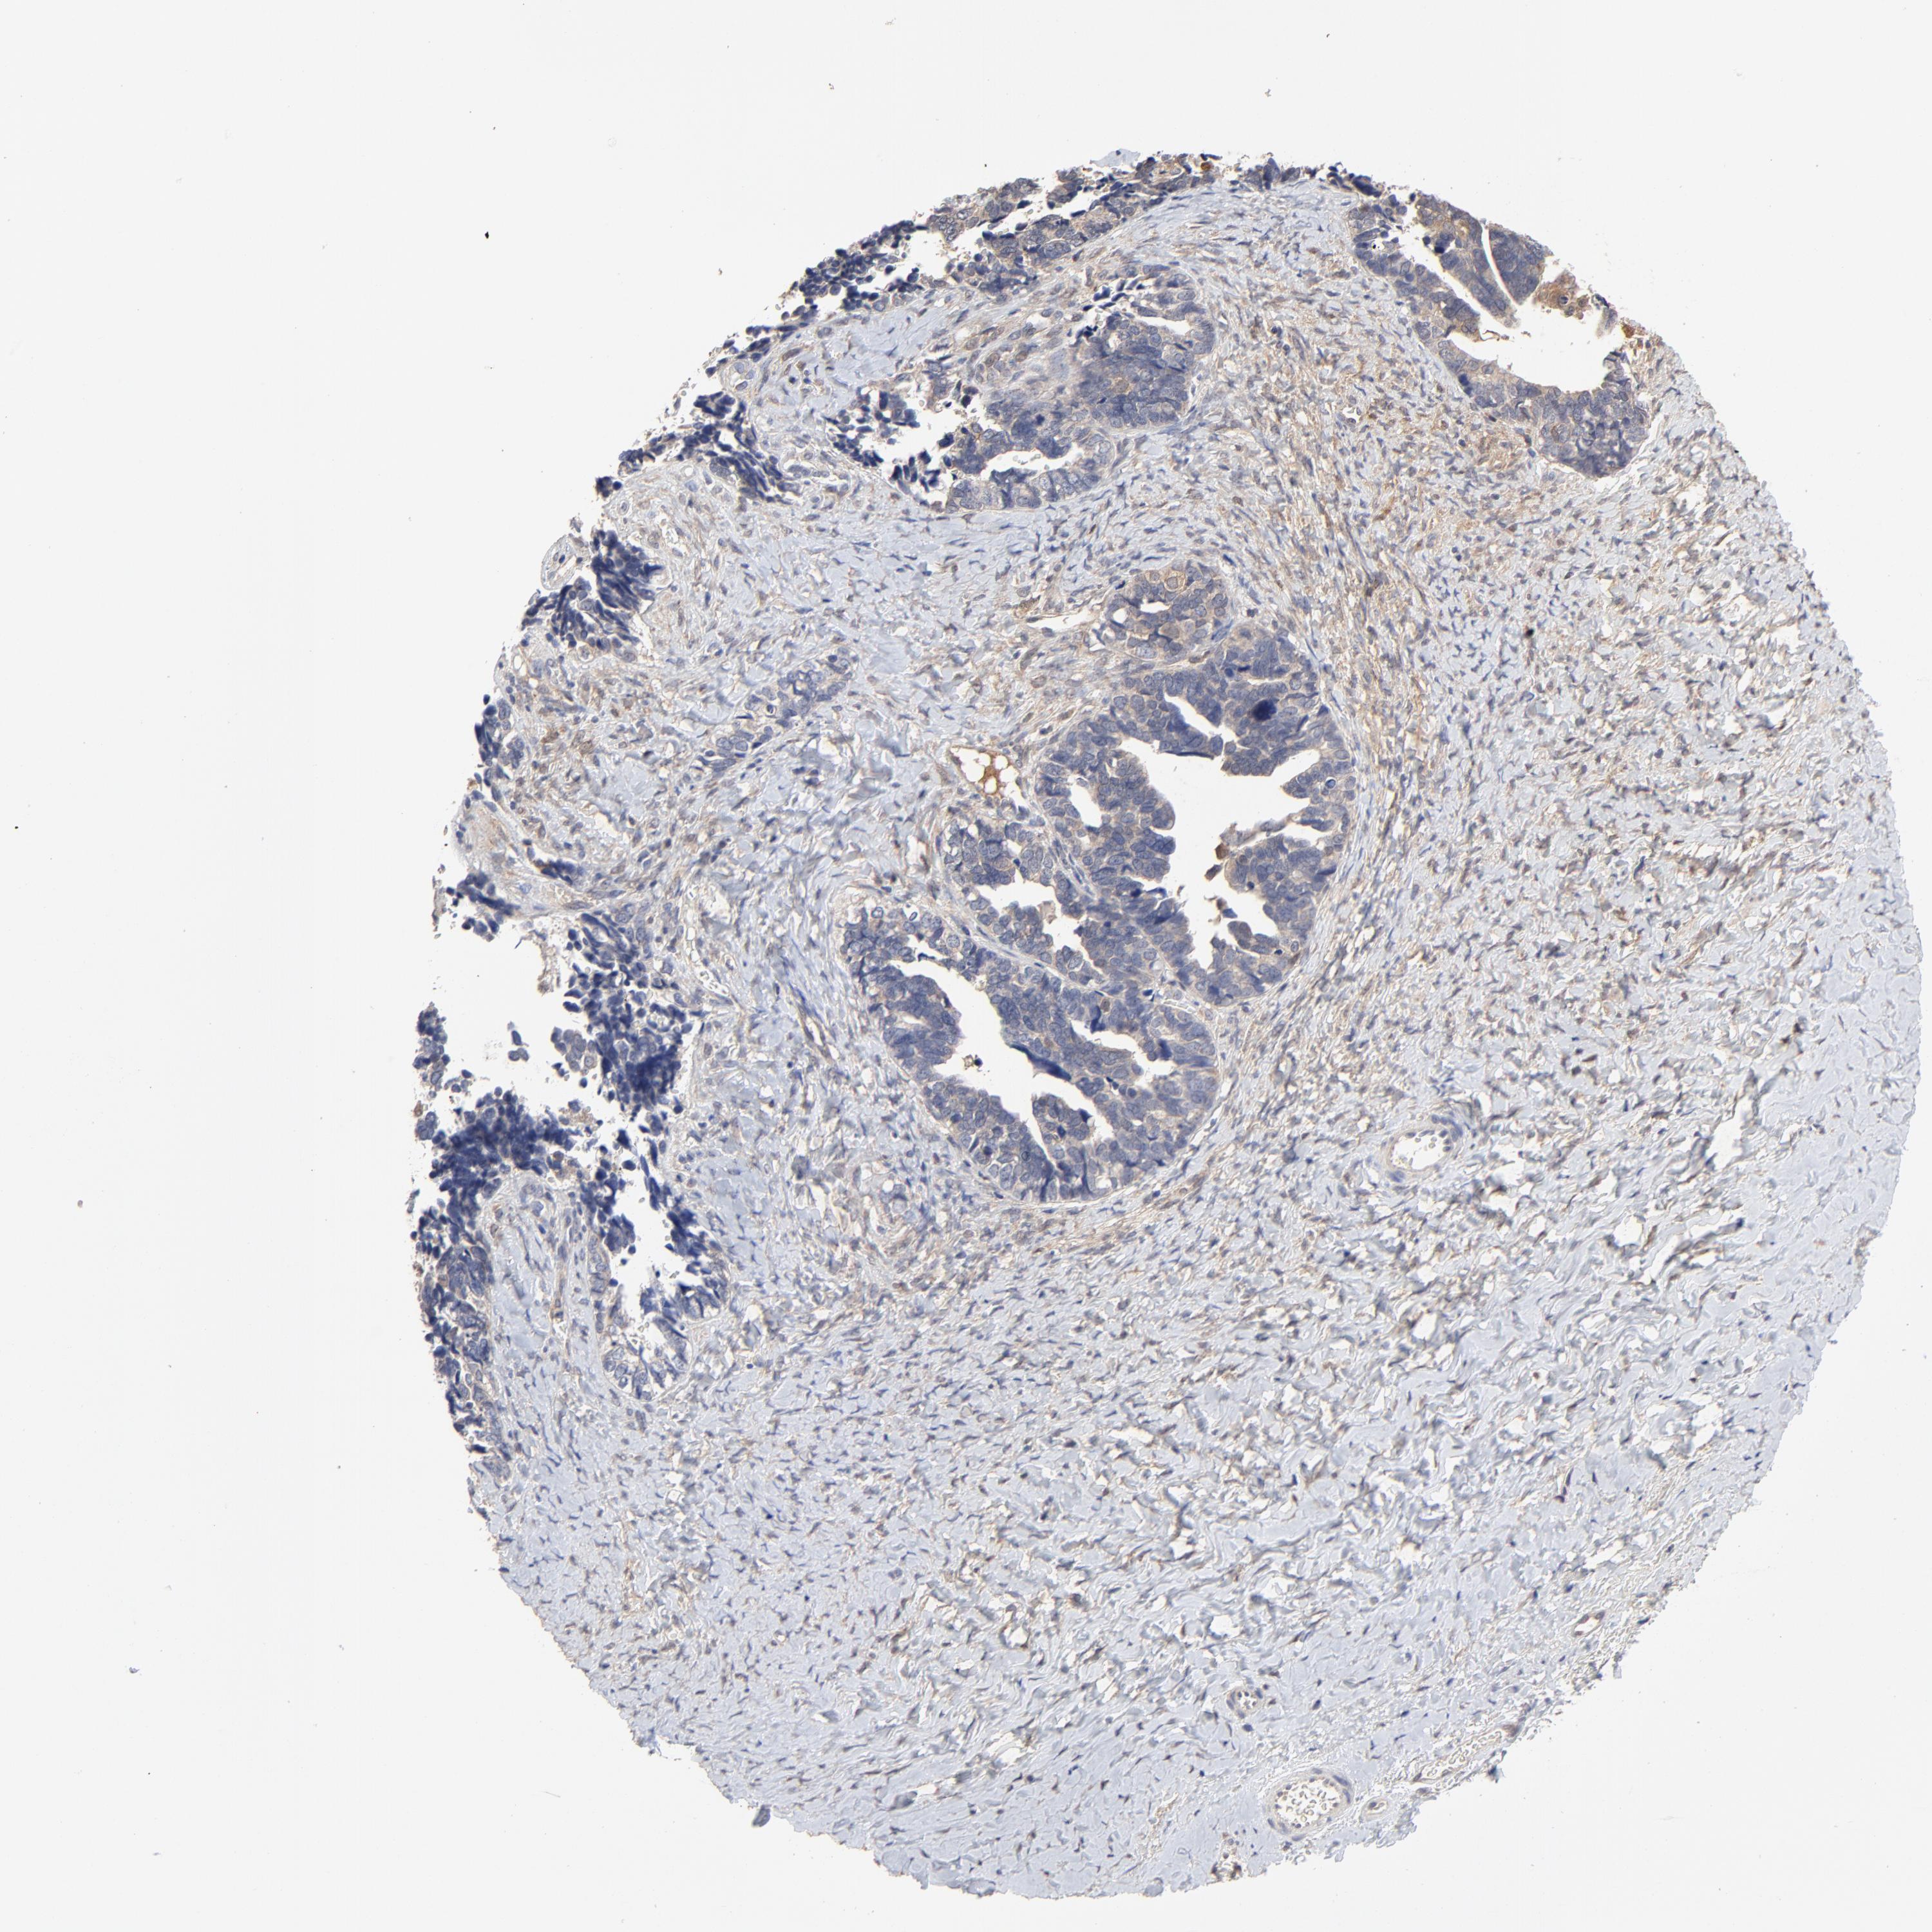

OVARIAN CANCER - Protein expressioni

A mouse-over function shows sample information and annotation data. Click on an image to view it in a full screen mode. Samples can be filtered based on level of antibody staining by selecting one or several of the following categories: high, medium, low and not detected. The assay and annotation is described here.

Note that samples used for immunohistochemistry by the Human Protein Atlas do not correspond to samples in the TCGA dataset.

Antibody stainingi

Antibody staining in the annotated cell types in the current human tissue is reported as not detected, low, medium, or high, based on conventional immunohistochemistry profiling in selected tissues. This score is based on the combination of the staining intensity and fraction of stained cells.

Each image is clickable and will lead to virtual microscopy that enables deeper exploration of all samples and also displays staining intensity scores, fraction scores and subcellular localization as well as patient and tissue information for each sample.

Antibody CAB005191

Cystadenocarcinoma, mucinous, NOS

Carcinoma, endometroid

Cystadenocarcinoma, serous, NOS

Carcinoma, NOS